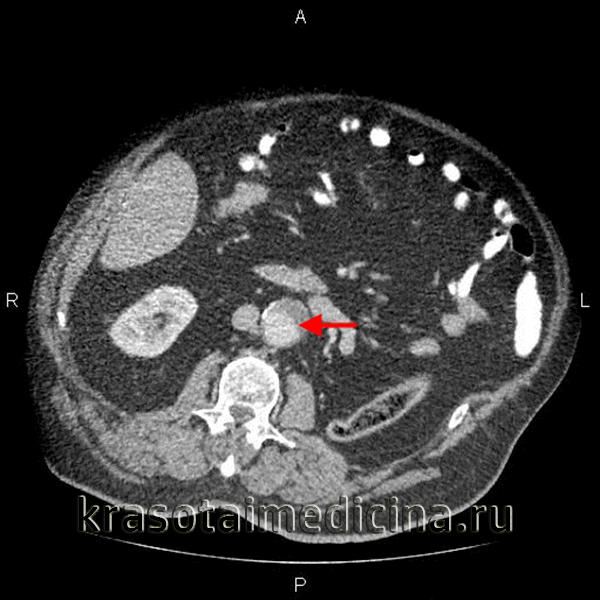

КТ-ангиография аорты. Аневризма брюшной аорты над бифуркацией. Просвет аневризмы (красная стрелка), пристеночный тромб (зеленая стрелка).